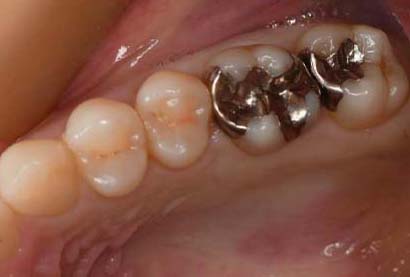

セラミックインレー、

※ 横にスクロールできます

| 年齢・性別 | 30代・男性 |

|---|---|

| 主訴 | 銀歯を白くしたい |

| 治療内容 | 金属除去、つめ物かぶせ物治療 |

| 治療期間 | 2週間 |

| 治療費用 | 総額 330,000円(税込) つめ物(セラミックインレー) 55,000円(税込) ×2 かぶせ物(ジルコニアステインクラウン) 110,000円(税込) ×2 |

| 副作用等 | 神経の治療 |

| 治療方針 | 金属を除去し中の虫歯を しっかりとりきりセラミックのつめ物 |

| 特記事項 | 金属の中は虫歯になっており、 症状がなかったが神経まで達していて 神経の治療が必要になったケースです。 |

| 担当者所見 | 一本ずつではなく同時にブロックで型取り、 色味合わせを行なったため精度、 審美面どちらも患者さまには満足していただけました。 |